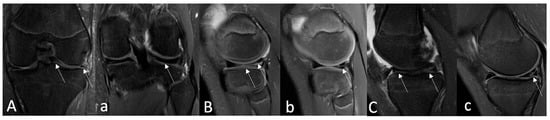

Signal alterations on postoperative MRI were rated according to Stoller and Crues’ three-stage classification. Grade 1 was defined as an intrameniscal signal with irregular margins that did not connect or communicate with the articular surface. Grade 2 was described as a linear signal that did not abut or connect with an articular surface. A linear or complex signal intensity that abutted or communicated with an articular surface was classified as Grade 3. In summary, grade 3 was deemed unhealed, grade 2 as partially healed, and grade 1 as fully healed due following MRI assessment [44,45]. A musculoskeletal imaging radiologist (A.B.) and an experienced orthopedic surgeon (V.B.M.) performed the MRI evaluation independently and blinded to functional and clinical evaluation. The intraclass correlation coefficient (ICC) was calculated for interobserver reliability. The overall consensus was reached for each case by both observers. Based on the MRI assessment, only cases with an MRI grade 3 evaluation were considered unsuccessful; therefore, MRI grades 1 and 2 were combined into one group as effectively healed meniscus following MRI, while MRI grade 3 was left separately as unhealed meniscus on MRI images. The postoperative MRI grades for all three groups are shown in Figure 5.

Figure 5. Examples of postoperative MRI assessment based on Stoller and Crues’ three-stage classification. (A)—Preoperative coronal PD-FSE, FS MR image shows (arrows) a bucket handle-type lateral meniscus tear in a 16-year-old boy. Twelve-month postoperative coronal (a) MR image shows a repaired lateral meniscus and no intrameniscal signal alterations (arrow)—classified as MRI Grade I using Crues and Stroller classification. (B)—A preoperative sagittal PD-FSE, FS MR imaging of an 11-year-old boy reveals (arrows) a complex (radial + longitudinal)-type lateral meniscus tear. Sagittal PD-FSE, FS (b) MR image obtained 12 months after surgery, where sagittal PD-FSE, FS (b) indicates (arrow) a partially healed lateral meniscus with persisting intrameniscal signal changes that do not extend into the joint space—classified as MRI Grade II using Crues and Stroller grading. (C)—A 14-year-old girl’s preoperative sagittal PD-FSE, FS MR imaging demonstrates (arrows) a medial meniscus tear of the bucket-handle type. Fourteen-month postoperative sagittal (c) PD-FSE FS MR images establish (arrow) an unhealed medial meniscus with signal changes extending within the joint space—classified as MRI Grade III using Crues and Stroller grading. MR—magnetic resonance; FSE—fast spin echo; FS—fat saturation.